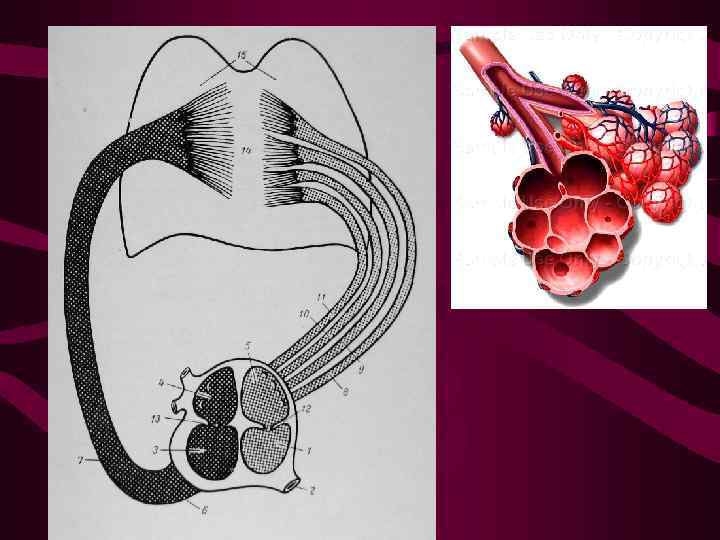

Рентгенанатомия малого круга кровообращения Р-изображение нормального легочного рисунка образовано за счет сосудов, в основном артерий Диаметр сосудов пропорционален интенсивности кровотока в них и в норме уменьшается от центра к перифирии

Рентгенанатомия малого круга кровообращения Р-изображение нормального легочного рисунка образовано за счет сосудов, в основном артерий Диаметр сосудов пропорционален интенсивности кровотока в них и в норме уменьшается от центра к перифирии

Артерии легких имеют дихотомическое деление как и бронхи уменьшаясь при каждом делении от центра к перифирии В центральных отделах легких находятся сегментарные артерии диаметром 2 -3 мм В норме легочный плащ не содержит сосудов более 1 мм в диаметре Бронхиальные артерии в рентгенологическом отображении легочного рисунка участия не принимают

Артерии легких имеют дихотомическое деление как и бронхи уменьшаясь при каждом делении от центра к перифирии В центральных отделах легких находятся сегментарные артерии диаметром 2 -3 мм В норме легочный плащ не содержит сосудов более 1 мм в диаметре Бронхиальные артерии в рентгенологическом отображении легочного рисунка участия не принимают